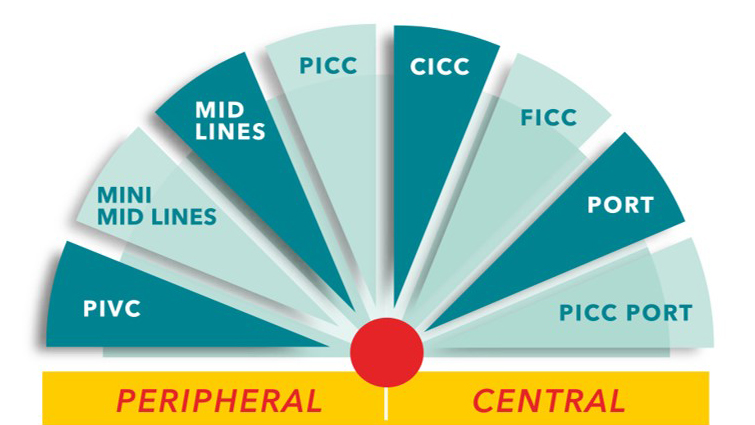

Vascular Access

Vascular Access

[/salt_icon_text][salt_icon_text]We have a strong track record of manufacturing high-quality medical devices for more than 21 years in 8 state-of-the-art manufacturing facilities across the world. Our products and types of equipment are designed to serve the medical facilities in treating people requiring vascular access.[/salt_icon_text]